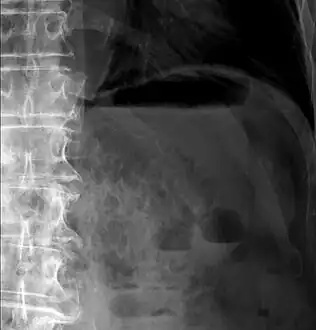

Pneumatosis intestinalis at computed tomography in intestinal ischemia. Lung window for better representation of the gas deposits in the intestinal walls. Coronal reconstruction.

Upright AP radiograph showing gas in the wall of the small bowel in the left upper quadrant indicative of pneumatosis intestinalis.